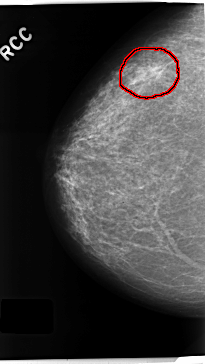

FILE: C_0230_1.RIGHT_CC.OVERLAY

TOTAL_ABNORMALITIES 1

ABNORMALITY 1

LESION_TYPE MASS SHAPE IRREGULAR MARGINS SPICULATED

ASSESSMENT 5

SUBTLETY 5

PATHOLOGY MALIGNANT

TOTAL_OUTLINES 1

BOUNDARY